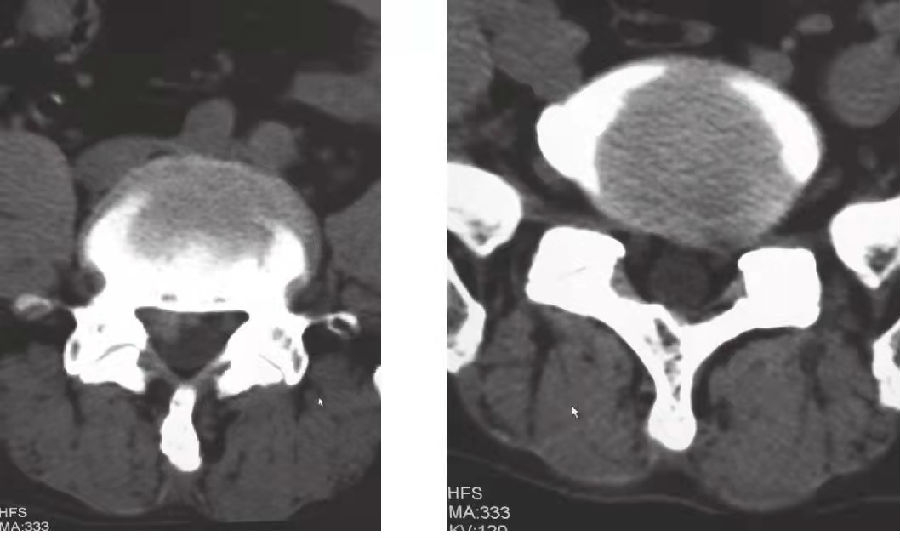

3.辅助检查:腰椎CT(图1)示L4/5椎间盘右后缘见软组织密度影,向椎管内隆起9.0mm,硬膜囊受压,填塞右侧侧隐窝。L5/S1椎间盘左后缘见软组织密度影,向椎管内隆起5.0mm,挤压硬膜囊,压迫左侧神经根。骨性椎管未见狭窄。

图1 患者腰椎CT

左图:L4/5椎间盘向右后出;右图:L5/S1椎间盘向左后突出